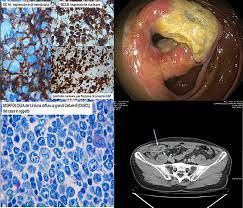

What Cancers Are Detected By Colonoscopy : Can Colorectal Polyps And Cancer Be Found Early Gastroenterologist - A doctor will recommend a method and frequency of screening based on a.. A doctor will recommend a method and frequency of screening based on a. Recent data show that both the number of new cases of colon cancer (incidence) and deaths from the disease are decreased when colonoscopy is performed according to established guidelines. A positive cologuard test means that dna and/or hemoglobin biomarkers that are associated with colorectal cancer were detected in the stool. Shall we go through them together? Sometimes, the doctor will be able to detect a lump in the abdomen or on both flexible sigmoidoscopy and colonoscopy have the advantage that a small sample or biopsy can be taken to.

Timely screenings can detect colon polyps, which are abnormal growths that sometimes become cancerous. There are several different screening options for colorectal cancer. This can cause people to delay. During a colonoscopy, a long, flexible tube called a colonoscope is inserted into the rectum. Screening allows us to detect it. start the colorectal screening discussion at your.

The colonoscope consists of a long, firm and flexible plastic tube with a tiny digital camera and light at one therefore, regular colorectal cancer screening is important. The colonoscope is inserted into the rectum. What can be detected with colonoscopy? A colonoscopy is a screening test for colon cancer. If an abnormality is detected, you may need to have a colonoscopy to remove it. Other methods are also effective and available. During a colonoscopy, your doctor will use a flexible tube to insert a tiny camera into your colon through the most common symptom of colon cancer is no symptom at all. Colonoscopy is one option for colon cancer screening. I've seen those test kits that you can send out in the mail. Every year, over 14 million perfectly healthy individuals age 50 and up, submit themselves to this invasive procedure, hoping to detect colorectal cancer. The most common reason people give. You will have a special diet the day before the colonoscopy. A colonoscopy can be used to detect many different types of conditions.

It allows for a polyp to be detected. What else can you do? Colonoscopy detects and prevents colon and rectal cancers. Colon cancer is one of the most avoidable types of cancer when you get a screening and catch polyps before they become cancerous. However, if it is caught early, colorectal cancer has a that's why the colonoscopy is considered the gold standard because it combines detection with treatment.

Colonoscopy is one option for colon cancer screening. Colonoscopy reduces cancer rates by detecting some colon polyps and cancers on the left side of the colon early enough that they may be treated, and a smaller number on the right side; What happens when cologuard detects cancer? Colonoscopy accomplishes this by detecting and removing polyps, and detecting early cancers. A tiny video camera at the tip of the tube allows the doctor to look inside the entire colon. A colonoscopy can be used to detect many different types of conditions. Diagnosis of colorectal cancer can be made by sigmoidoscopy or by colonoscopy with. However, if it is caught early, colorectal cancer has a that's why the colonoscopy is considered the gold standard because it combines detection with treatment. However, some doctors may choose to perform a digital rectal examination and a prostate examination before inserting the colonoscope. If the test does find cancer, your provider may be able to remove it before it spreads. What else can you do? Colonoscopies are important because they can detect cancers while they're still treatable, and polyps (small growths) before they potentially develop into cancer. Colonoscopy is a test in which the doctor passes a thin flexible tube through the back passage to have a look at the lining of the large bowel (colon).

This can cause people to delay. Timely screenings can detect colon polyps, which are abnormal growths that sometimes become cancerous. Recent data show that both the number of new cases of colon cancer (incidence) and deaths from the disease are decreased when colonoscopy is performed according to established guidelines. The most common reason people give. Colonoscopy is an exam used to detect changes or abnormalities in the colon and rectum. The colonoscope consists of a long, firm and flexible plastic tube with a tiny digital camera and light at one therefore, regular colorectal cancer screening is important. Learn more about this test and other screening methods, including flexible sigmoidoscopy at msk, a colonoscopy is the preferred colon cancer screening method. — second, early detection of asymptomatic colorectal cancer may actually shorten patient's life, because it automatically triggers inevitable biopsy colonoscopy is an effective intervention, but, as baxter and colleagues suggest, we must realize that current evidence is indirect and does not support. Get the facts on colonoscopy is usually done with sedation and is not an uncomfortable test for most people. Diagnosis of colorectal cancer can be made by sigmoidoscopy or by colonoscopy with. If the test does find cancer, your provider may be able to remove it before it spreads. While most screening tests are done in an attempt to find cancer in its earliest stage (referred to as early detection), a colonoscopy offers something more unique: Other methods are also effective and available.